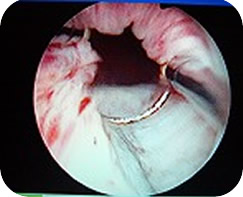

手術前は大いに緊張したものの、実際始まってみると暖かい部屋で音楽を聞きつつモニタを見ながらの手術。なんてハイテク。メスも使わず全身麻酔じゃないので意識はあるが痛みは全くナシ。その上このモニタ映像はDVDでお土産にもらえるし・・・なんだかSM。ちがったSF。

手術後の感じなど 出口方面がちょっと・・・ 術後初めての自力排尿の時には、痛みと共におしっこに混ざっていろいろとグロいものがどばっと出て気を失いかけましたが、初おしっこはそんなもんなんだそうです。 その後は徐々に楽になりましたが、退院後もひと月以上、排尿の度に出口に痛み〜熱感があってつらかった。下の画像は術後40日も経ってからオシッコと共に出てきたグロいもの。こういうサプライズもあるということです。